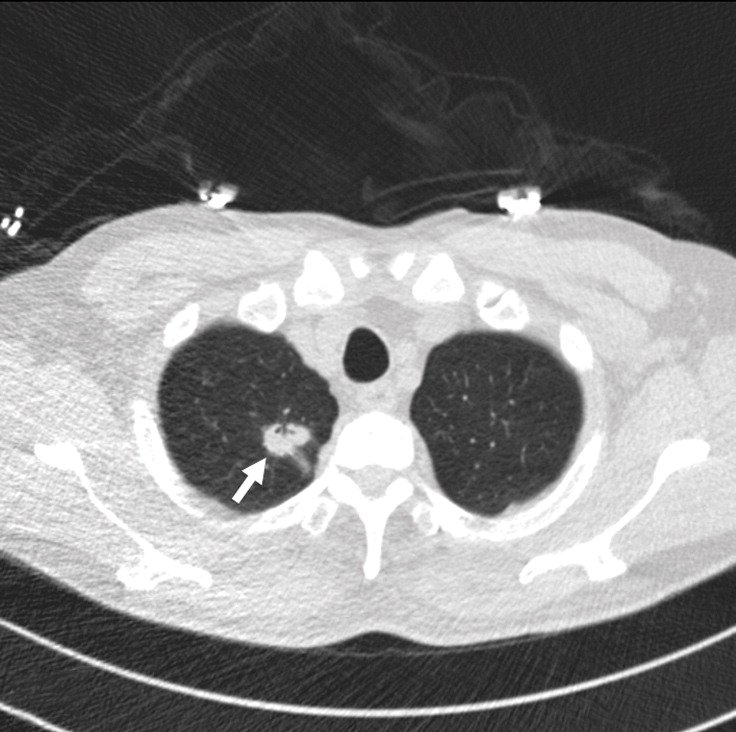

Example 2 shows an example CT scan of a 63-year-old with some of the characteristics described above. The nodule in the scan is small and close to a group of vessels of the upper left lung that partially block it from view, which caused the radiologist reading the scan to miss the tumor. The tumor was detected using a chest x-ray two years later.

Example 2: 63 year old patient with a cancerous lung nodule